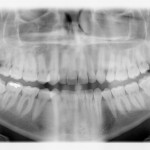

Denti inclusi: prevenzione, diagnosi, terapie e prognosi

Riassunto

Introduzione. L’inclusione dentaria è molto frequente nella pratica odontoiatrica, colpisce dal 5,6 al 18,8% della popolazione generale e circa il 20-22% dei pazienti ortodontici e, nella...